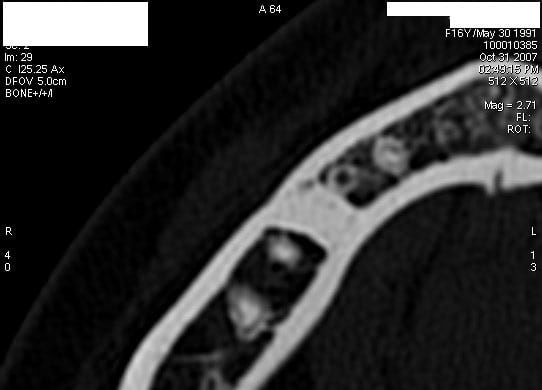

A priori, vu la densité, une traversée d'os cortical. Rien de spécial à faire. Exemple en pièce jointe. Refaire une radio dans 1 an pour le principe.

Corticale2 gt3604 - Eugenol

Corticale1 tfvxho - Eugenol